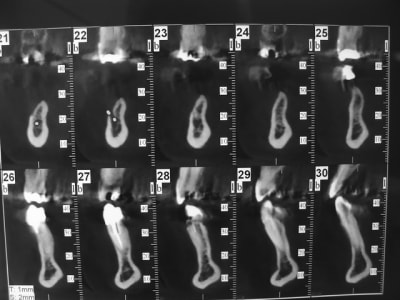

Patiente agée d'une trentaine d'année. En bouche la crête osseuse est inapparente et absence de gencive attachée.

Dans les secteur d'emmergence du nerf mandibulaire la palpation est douloureuse.

coupe_sect_4_c0hkw3.jpg

sinon secteur 3 y a peut être moyen dans certaines zones de travailler avec l'expansion...mais pas facile comme cas...surtout si la demande esthétique est +++

1. 2 séances d ostéotension

2. Epaississement vestibulaire en zone molaire nanobone prfd jason

3. pose de 2 cylindres enfouis en 34 44

4. pose de monodisk en 36 37 46 47 enfouis bloqués par vis ostéosynthèse

Mouais! Mais elle veut la hauteur en plus.

Justement c'est la laxité du lambeau qui m'inquiète +++++

Bien vu! Je ne connaissais pas. C'est le même cas. J'aurai bien tenté mais ce qui "m'inquiète", c'est l'emmergence du mandibulaire. Sur le modèle du site je ne le vois pas; sur mon cas il serait juste au niveau du premier bloc et je me pose la question du surplomb ou de "l'irritation" possible.

On vois le mentonnier, mais je ne sais pas pour ton cas. pour avoir une bonne laxité du lambeau, il est necessaire de dissequer le mentonnier sur 8-10 mm, ( jamais fait, mais j'ai vu faire... )

Bien vu! Mais je reconnais je flippe pour la position de l'emmergence du mandibulaire. J'ai peur de le coincer, j'ai déjà vu des cales osseux sans compter la peur de déchirure des sutures. La tunélisation ne me semble pas possible de ce fait.

J'ai fait part du cas (et vais encore le faire ce jeudi) à un maxillo: je cite "ouh la la t'emmerdes pas! c'est craingnos, il faut disséquer et déplacer l'emmergence"

Nous avons traité un cas comme ça avec D57,(secteur 3) os D1, manque de largeur résultat (de mémoire je n'ai pas les photos ici) 2 implants en même temps que l'expansion (34/37) et la suite 3 mois après le déplacement des volets vestibulaires, (bloqués sans vis) mais protégés par un bridge provisoire.

En conclusion, ce n'est pas un cas ou je ferais une greffe même pré ajustée (résultats en Décembre Pluton), mais une expansion sans doute avec déplacement/fracture du volet vestibulaire car os D1, mais si ça ce passe bien simple bone splitting et pose des implants dans la séance.